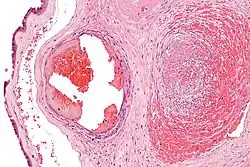

Excessive generation of fibrin due to activation of the coagulation cascade leads to thrombosis, the blockage of a vessel by agglutination of red blood cells, platelets, polymerized fibrin and other components. Ineffective generation or premature lysis of fibrin increases the likelihood of a hemorrhage.

Fibrin is formed after thrombin cleavage of fibrinopeptide A (FPA) from fibrinogen Aalpha-chains, thus initiating fibrin polymerization. Double-stranded fibrils form through end-to-middle domain (D:E) associations, and concomitant lateral fibril associations and branching create a clot network.[5][6] Fibrin assembly facilitates intermolecular antiparallel C-terminal alignment of gamma-chain pairs, which are then covalently 'cross-linked' by factor XIII ('plasma protransglutaminase') or XIIIa to form 'gamma-dimers'. The image at the left is a crystal structure of the double-d fragment from human fibrin with two bound ligands. The experimental method used to obtain the image was X-ray diffraction, and it has a resolution of 2.30 Å. The structure is mainly made up of single alpha helices shown in red and beta sheets shown in yellow. The two blue structures are the bound ligands. The chemical structures of the ligands are Ca2+ ion, alpha-D-mannose (C6H12O6), and D-glucosamine (C6H13NO5).[7]